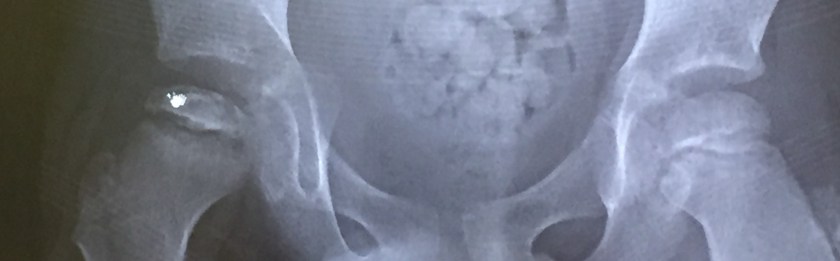

Nov scan1

X-ray image